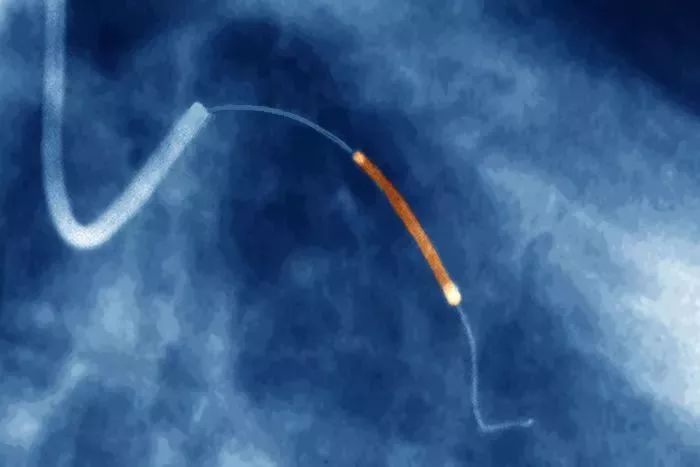

科学家的“自我实验”史521 / 作者:UFO爱好者 / 帖子ID:85718

一根导管和支架(橙色)被放置在心脏里,用于治疗心脏病。

今天,我们使用所谓的心脏导管术来诊断和治疗心脏疾病,如血管栓塞。“这个手术现在在全世界每年使用超过 50 万次,”克里奇教授说。